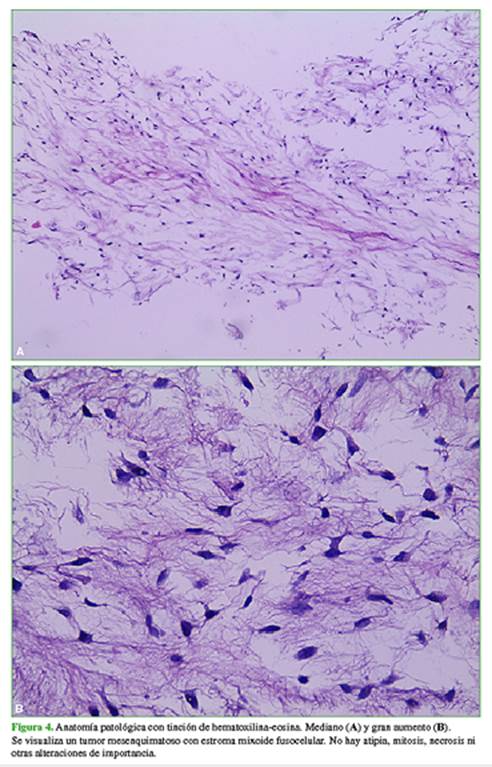

Ante la sospecha de una asociación entre lesiones óseas, interpretadas como displasia fibrosa y lesión de partes blandas, se solicita una biopsia de la masa de partes blandas (Figura 3), con confirmación histológica de mixoma intramuscular (Figura 4), que configura un síndrome de Mazabraud.

Las radiografías son normales, aunque los mixomas intramusculares se pueden manifestar con calcificaciones no específicas en partes blandas. En la ecografía, los mixomas intramusculares se visualizan como masas ovoideas, poco definidas e hipoecoicas, con posibles áreas quísticas. En la tomografía computarizada, aparecen como lesiones hipointensas con pared que las separa del tejido muscular. En la resonancia magnética, se visualizan como lesiones hiperintensas en las secuencias T2, gradiente de eco o STIR. Las secuencias T1 muestran baja señal.2,6-9